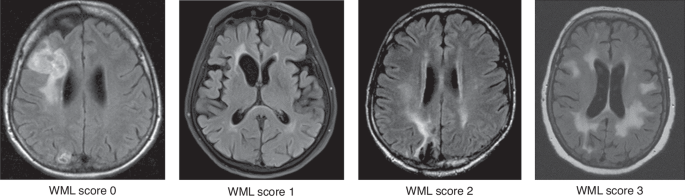

cMRIs acquired at the following time points were reviewed: shortly before (baseline) and three months after receiving HDC/ASCT (post-HDC, maximum delay 14 days); at 12, 24, 36, 48, and 60 months (m12–m60) after the treatment, and for long-term survivors the last available imaging (>m60). After the review of the complete imaging protocol, T2-FLAIR images were rated visually for the presence of WML by a neuroradiologist (VR, 10 years of experience in neuroimaging) who was blinded to clinical information. A WML score at each imaging time point was defined using the Fazekas score for deep WM (FS-DWM, range 0–3) and periventricular WM (FS-PWM, range 0–3) as well as the modified Fazekas score (mFS, range 0–3) for the summarized WML burden (average of maximum of FS-PWM and FS-DWM, Fig. 1) [26]. WML assessment did not include lesions such as tumor infiltration, edema or post-therapeutic/-ischemic gliosis. Patients were assigned to a low (mFS 0–1) or a high WML burden (mFS 2–3) group. We calculated the maximum mFS change over time and documented the time point of any mFS conversion from low to high. Additionally, global cortical atrophy (GCA, range 0–3) and mesial temporal atrophy (MTA, range 0–4) were visually assessed at each time point [27]. For the DWM, PWM, mFS, GCA, the pathological threshold score was ≥2, for MTA, the threshold was ≥2 in patients younger than 75 y and ≥3 in those older than 75 y.